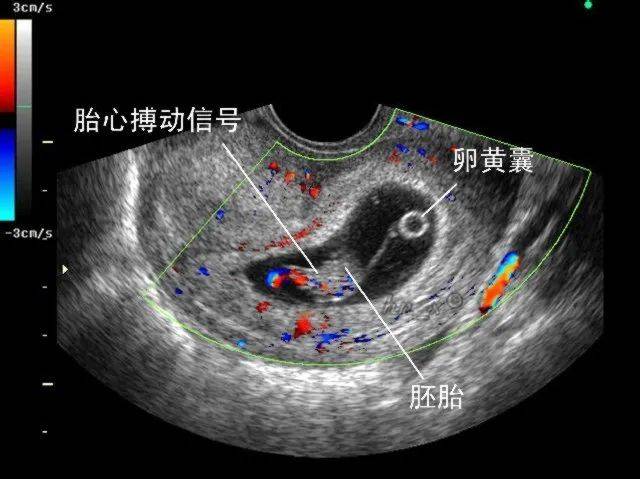

如果平时女性月经比较规律的话,在确定怀孕后,一般是在最早停经35天前后就可以在超声上发现胚芽,但是如果有些孕妇会到40--45天才能发现孕囊。

胎心出现时间一般会比胚芽出现的时间晚,而且大部分孕妇在妊娠45--50天可看到胎心,有些孕妇能要到50天以后才能发现胎心(考虑着床晚造成的)。